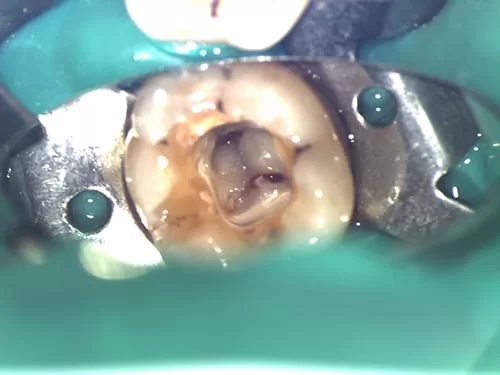

(3) 顯微鏡攝影畫面

術前 (左下第一大臼齒)

術後 (左下第一大臼齒)

術前 (左下第二大臼齒)

術後 (左下第二大臼齒)